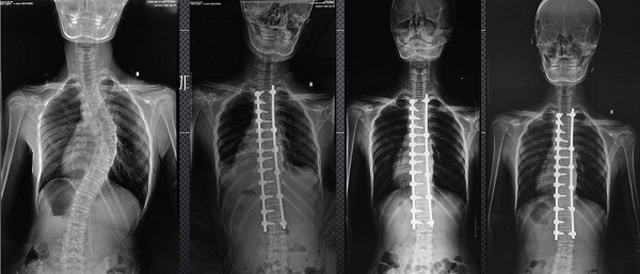

(7)全身拼接功能對(duì)有較大尺寸全脊柱拼接圖接桂成金下股分成幾次拍攝,再經(jīng)過(guò)秋件開(kāi)在骨科開(kāi)展的全脊柱畸形矯治工作中,雖然CT. MRI也能獲取全脊柱影像,接圖像,以便于長(zhǎng)度、角度、力線(xiàn)等測(cè)量和察脊柱在重力情況下但不能進(jìn)行立位檢查,無(wú)法觀(guān)全景觀(guān)察。全身拼接功能是高等級(jí)DR攝取患者立位全下的功能狀態(tài)圖像,因此采用動(dòng)態(tài)醫(yī)院特別看重的動(dòng)態(tài)DR功能之一。注:圖中Cobb脊柱正側(cè)位圖像是首選的檢查方法角度的大小是反映側(cè)彎嚴(yán)重程度的一個(gè)標(biāo)準(zhǔn)。